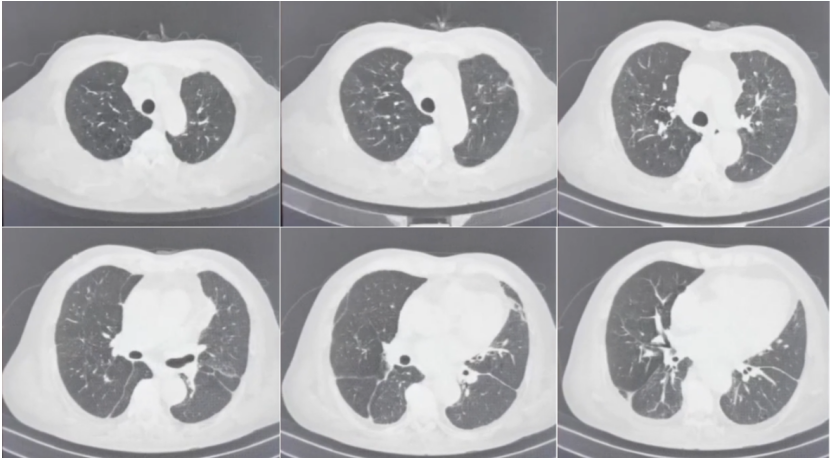

5月8日复查胸部CT可见空洞样病变较前有所吸收; 6月9日复查病灶进一步吸收10月9日随访胸部CT见病灶基本完全吸收(图15)

图片

15  患者病程中胸部CT对比